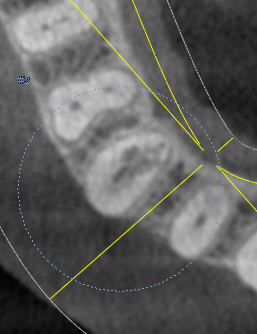

J'ai pensé d'abord à une résorption interne mais depuis que j'ai une 3d j'hésite.

je ne vois pas de continuité évidente entre la pulpe et la déminéralisation dentinaire

la déminéralisation n'est pas homogène mais lacunaire, quelle pourrait être son origine?

Resorption externe et pas interne.

si c'était une résorption externe il y aurai disparition du ligament or il est présent tout autour de la dent.